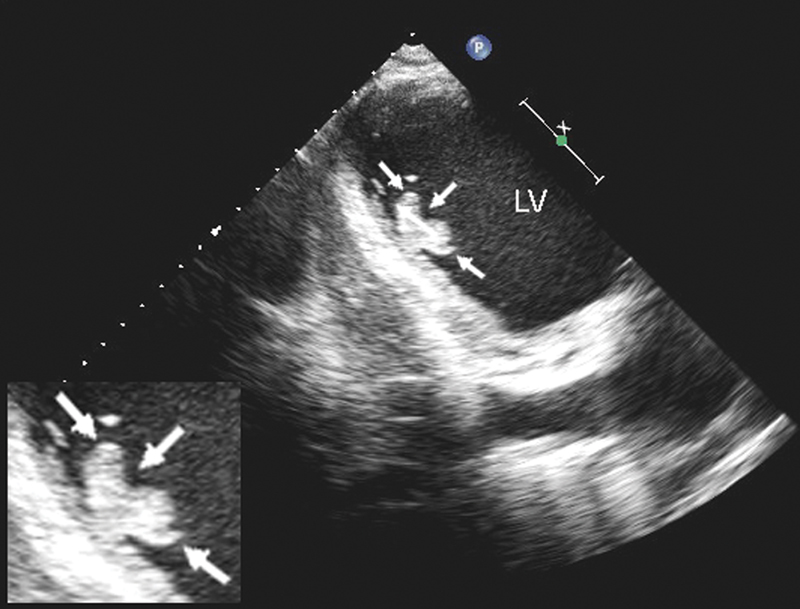

فحوصات تشخيصية لبعض امراض القلب والشرايين التاجية